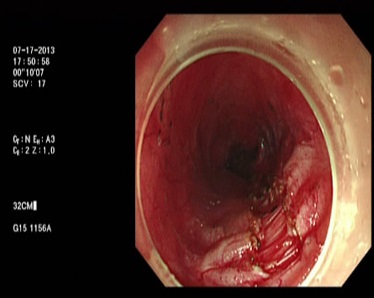

相關照片/影片

Photo Credit: Hitomi etc, Digestive Endoscopy 2015;27: 175–181